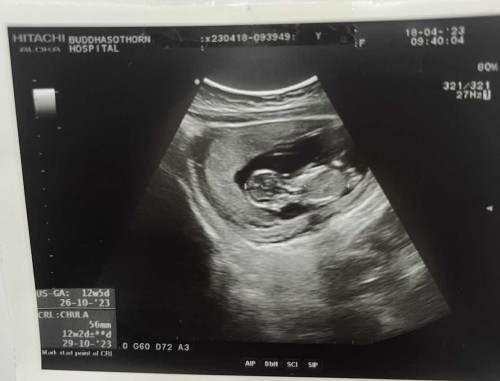

รูปภาพแรก ได้ 4 week รูปภาพที่ 2 ได้ 12 week 3 day น้องโตตัวใหญ่ไปไหมคะ ? หรือ ปกติของทารกในครรภ์คะ ? แม่ๆท่านไหนทราบมาแชร์ประสบการณ์กันหน่อยค่ะ ท้องแรก เลยไม่ค่อยทราบอะไรค่ะ ❤️

ขนาด 5.60 ซ.ม ขนาดปกติค่ะ 12วีคควรมีขนาด 5.40 ซ.ม. ขึ้นไปค่ะ